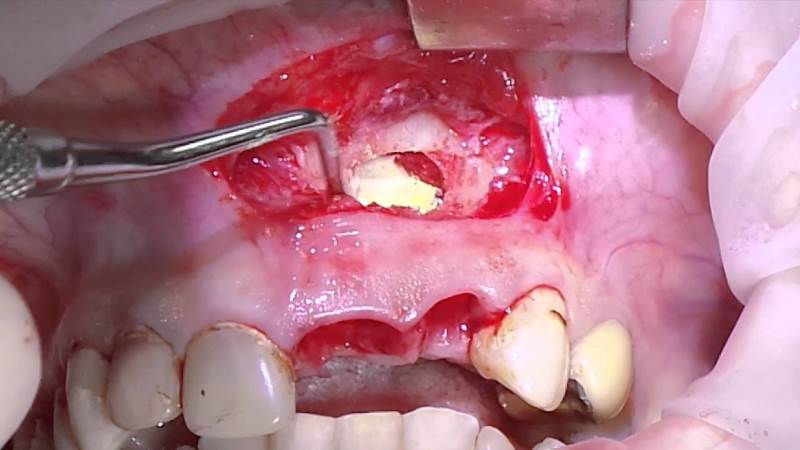

Если киста в челюсти продолжает расти после проведенных процедур, врач может применить апикальный хирургический метод лечения. Во время этой процедуры хирург очищает содержимое кисты и удаляет инфицированный корневой кончик зуба. Затем проводится пломбирование изнутри и разрез сшивается. Если киста в нижней или верхней челюсти образуется повторно, то может потребоваться удаление зуба и установка имплантата. Современные стоматологические методы позволяют решить эту проблему, сохраняя при этом зуб.

Хирургическое удаление кисты может вызвать осложнения как в челюсти, так и в организме в целом. Часто встречающимися осложнениями являются кровотечение, возникающее из-за повреждения крупного сосуда во время операции, перелом верхней челюсти при удалении травмированного зуба (в таких случаях используется зубодесневая шина), а также травмы гайморовых пазух, возникающие при отклонении слизистой оболочки придаточных носовых пазух при удалении увеличенной кисты зубов или деформации с образованием гайморита.